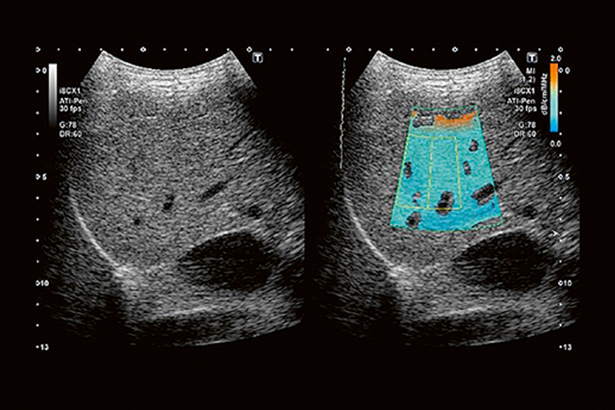

聲衰減成像為脂肪肝、肝纖維化的無創診斷提供定量工具。